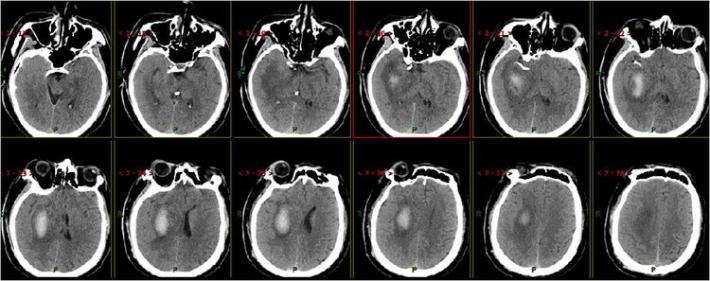

术后即刻复查头部CT

术中术后给予盐酸替罗非班应用12小时,桥接阿司匹林0.1g、氯吡格雷75mg,权衡利弊,未因核心梗死区出血转化停用抗血小板聚集药物。

患者术后1天,左侧肢体肌力0级,NIHSS评分:12分,复查头部CT:右侧基底节区出血,范围约22mmX49mm,请脑外科会诊:做好立体定向穿刺准备,注意观察患者病情变化,密集复查头部CT。

术后3天复查头部CT

术后7天复查头部CT

术后15天复查头部CT

术后21天复查头部CT